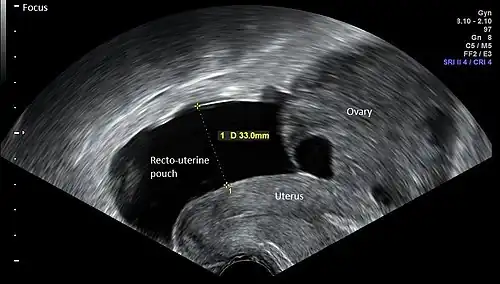

Vaginal ultrasonography in the sagittal plane in a woman with mild OHSS, showing a 33 mm wide anechogenic area behind the uterus in the recto-uterine pouch, which means there was ascites, that is, free fluid in the peritoneal cavity. Normally, there is up to 5 ml of fluid in the recto-uterine pouch,[5] corresponding approximately to an area up to 10 mm wide. The ovary measured up to 6.5 cm in diameter. |